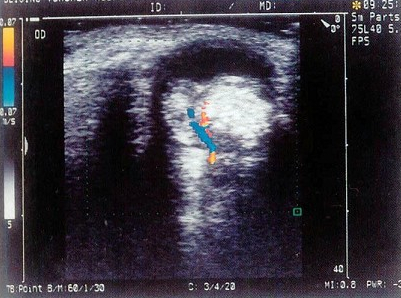

29、单项选择题

如图,根据胎儿颈部声像图,最可能的诊断是()

A.脊柱裂

B.脑膜膨出

C.淋巴管囊肿

D.单脐动脉

E.正常图像